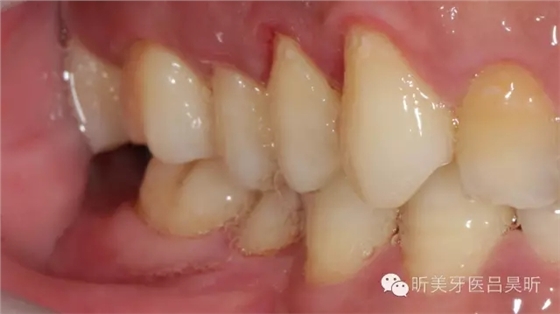

術(shù)前口內(nèi)檢查,可見牙槽骨寬度良好,角化齦量適中

術(shù)前口內(nèi)掃描,設(shè)計冠修復(fù)方式和種植位點